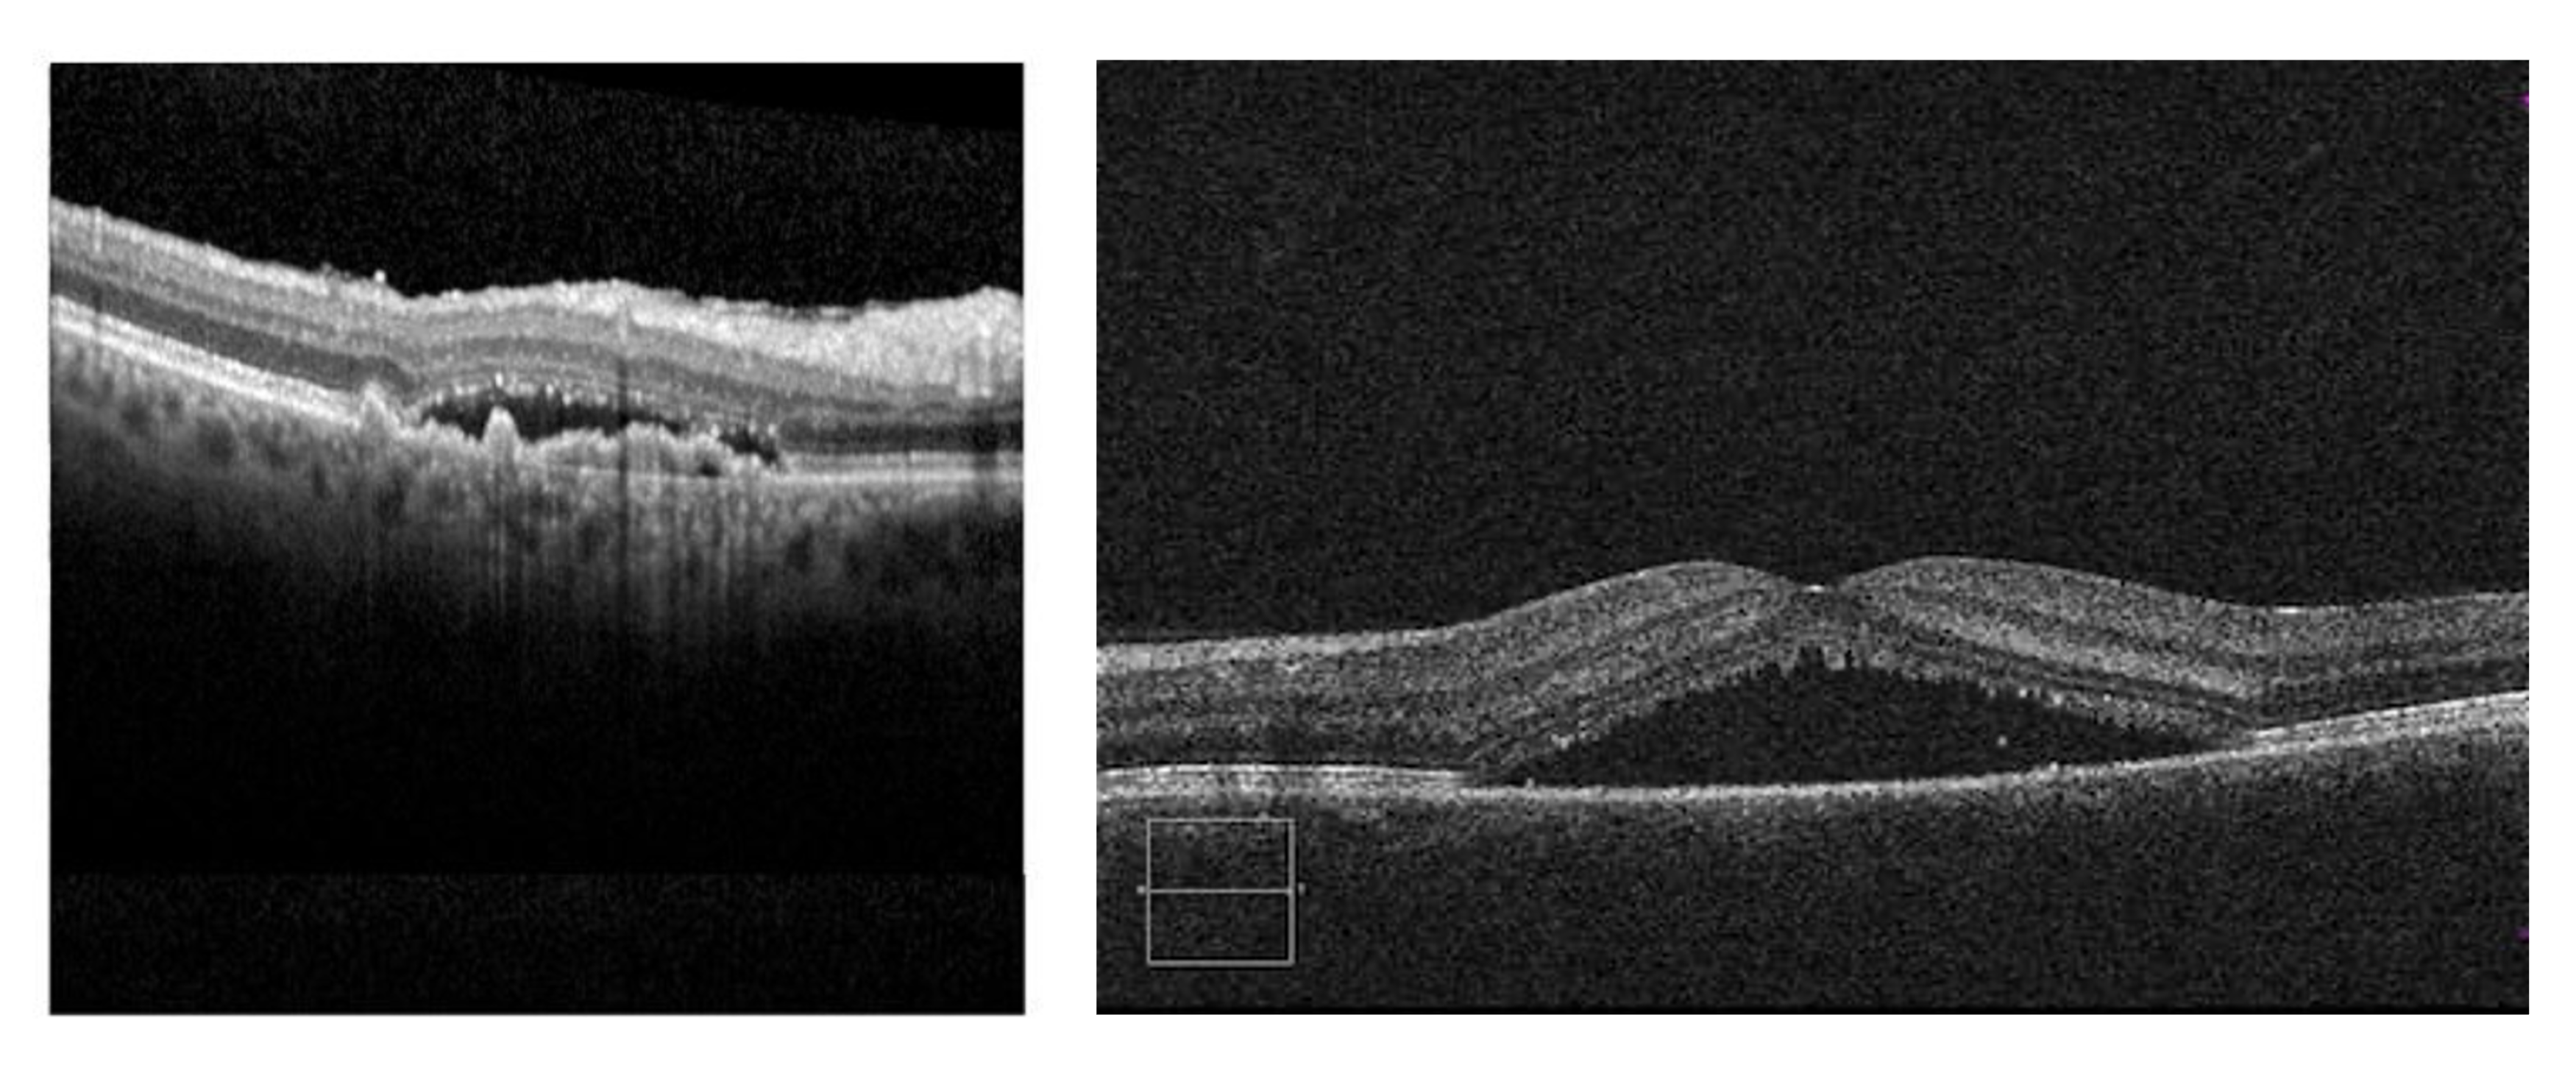

Wet AMD or CSR? Use OCTA